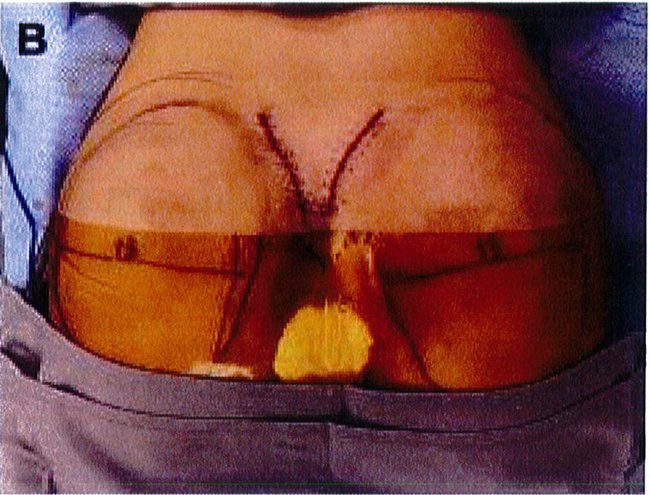

Tiêm tê dưới da bằng hỗn hợp lidocain 2% với epinephrine sau đó thêm ropivacain 7.5%. Trên lỗ hậu môn 5cm, rạch hai đường mỗi đường dài 6cm về hai phía mông cho tới khi tiếp cận được lớp cân mạc ở bờ ngoài xương cùng. Từ vị trí đó, tiếp tục rạch một đường dài khoảng 8-10 cm song với bờ ngoài xương cùng, đi lên trên và cong lõm về phía mông tương ứng để bộc lộ lớp dưới cân (Hình 8).

Hình. 8. (A) Phẫu thuật được lên kế hoạch, sử dụng các tiêu bản phù hợp với vùng mông của bệnh nhân với các đường rạch dài 6cm ở hai bên, trên vị trí hậu môn ít nhất 5cm. (B) Đây là hình ảnh bệnh nhân với tiền sử có bệnh lý liên quan vùng mông, đồng thời đã từng thực hiện hút mỡ mông trước đó, nên chúng tôi quyết định đặt đường rạch cao hơn bình thường để tránh các biến chứng.